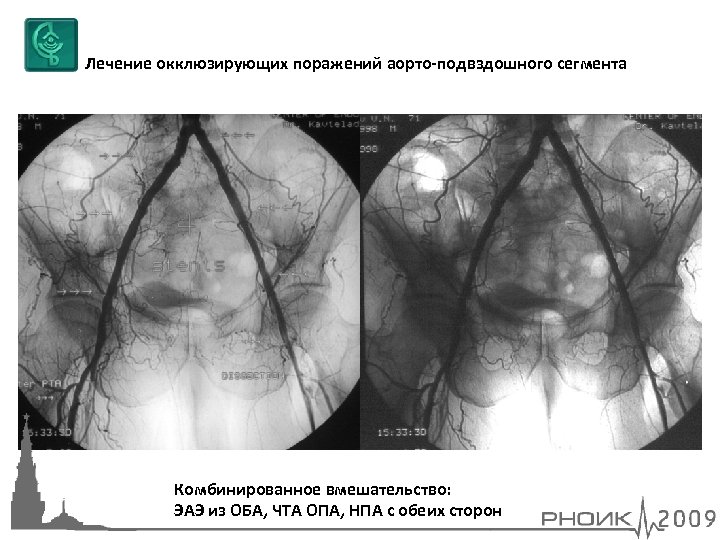

Лечение окклюзирующих поражений аорто-подвздошного сегмента Комбинированное вмешательство: ЭАЭ из ОБА, ЧТА ОПА, НПА с обеих сторон